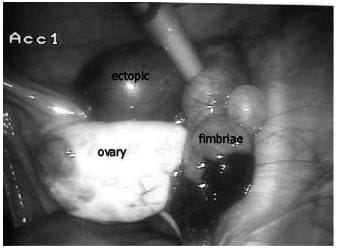

A laparoscopic image showing an isthmic tubal ectopic pregnancy with bleeding from the fimbrial end of the tube.

- At laparoscopy an unruptured ectopic pregnancy typically presents as a well-defined swelling in the Fallopian tube.